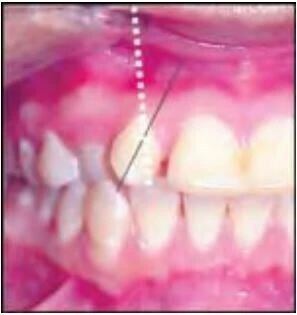

Thuật ngữ này dùng để chỉ những trường hợp hai răng bị đổi chỗ cho nhau, chẳng hạn răng nanh đổi vị trí cho răng cửa bên.